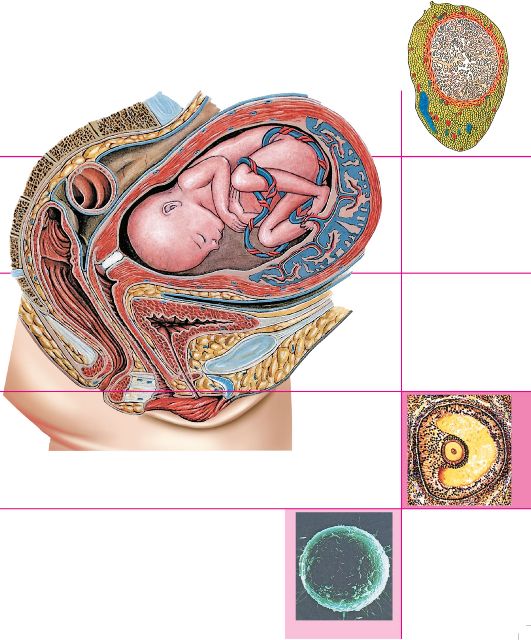

Физиология беременности: строение органов

Раздел: Моменты озарения